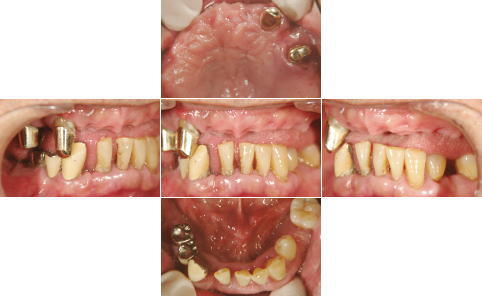

| 治療前 | 治療後 |

| 上顎はいつ抜けてもおかしくない状態であったため、直ちにAll-on-4を施術しました。 下顎も重度の歯周病で状態は良くありませんでしたが、患者様の希望もあり、抜歯せず、現在経過観察中です。 |